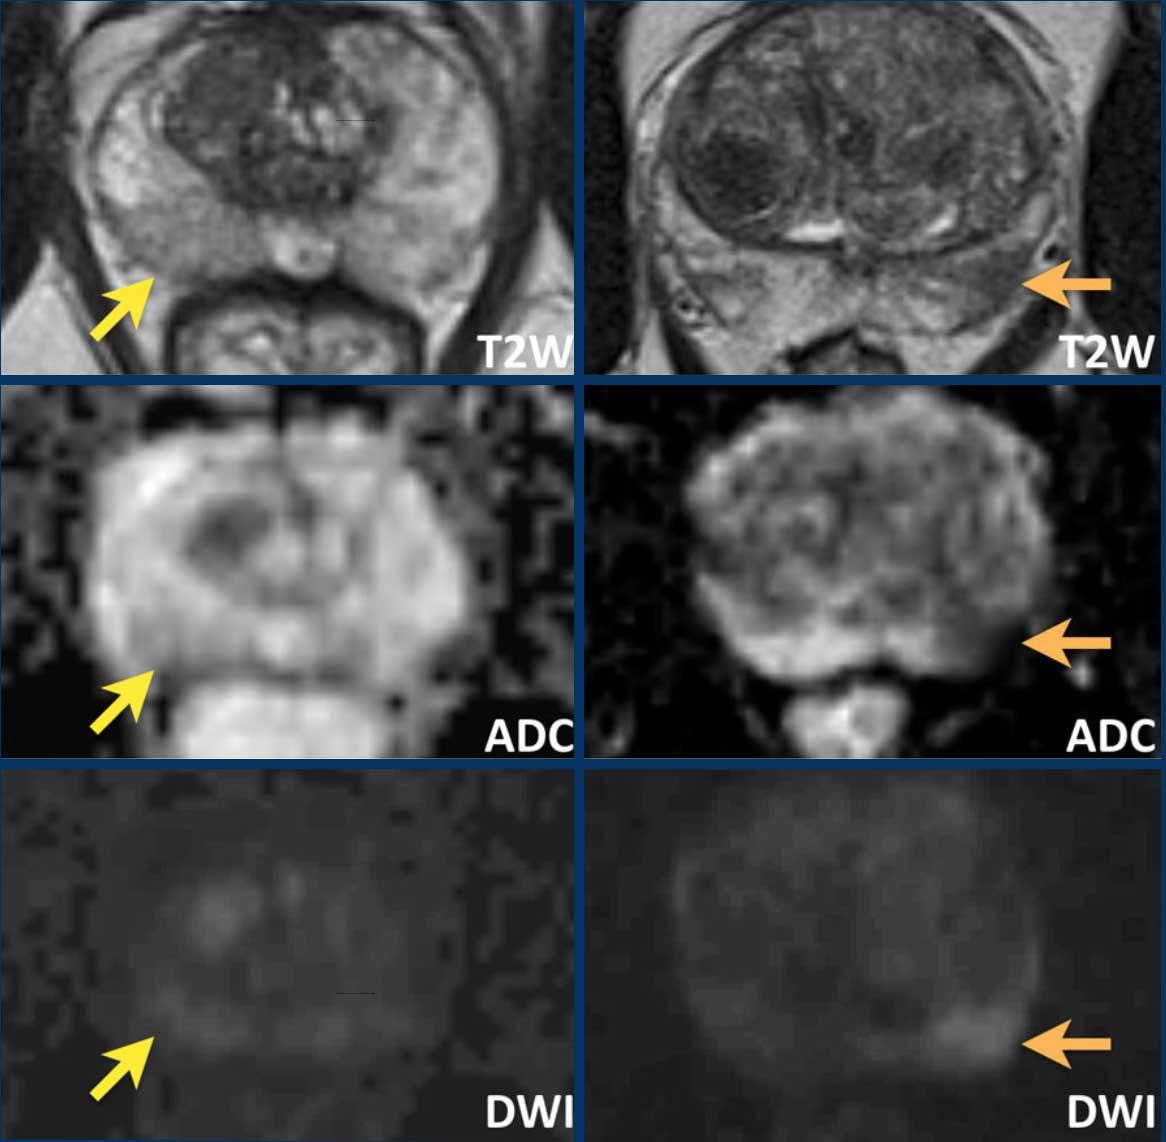

Ở đây chúng ta thấy sự khác biệt giữa viêm tuyến tiền liệt (hình bên trái) và ung thư tuyến tiền liệt (hình bên phải).

Bên trái

Các hình bên trái cho thấy một vùng hình nêm giảm tín hiệu nhẹ trên chuỗi xung T2W và ADC mà không có tín hiệu cao tương ứng trên DWI, nằm ở phía lưng trong vùng ngoại vi bên phải của phần giữa tuyến tiền liệt (mũi tên vàng).

Được diễn giải là viêm khu trú (phân loại PI-RADS 2).

Không thực hiện sinh thiết.

Bên phải

Các hình bên phải cho thấy ung thư tuyến tiền liệt có ý nghĩa lâm sàng với vùng giảm tín hiệu rõ rệt, bờ không rõ trên chuỗi xung T2W và ADC, và tăng tín hiệu khu trú trên DWI ở phía lưng trong vùng ngoại vi bên trái (phân loại PI-RADS 4).

Sinh thiết có hướng dẫn MRI cho thấy điểm Gleason 4+3.